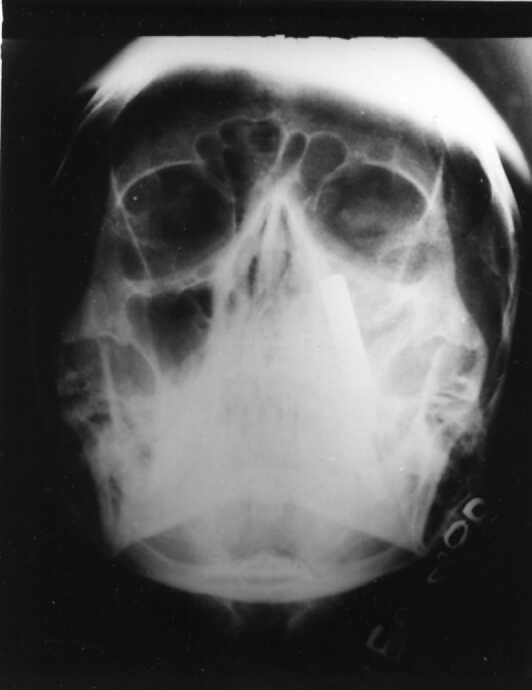

X-ray Paranasal Sinus revealed a radio-opaque shadow resembling a bullet abutting the medial wall of left maxillary sinus. All other walls of the antrum were intact.

Maxillary sinus is the largest of the paranasal sinuses and occupies the body of Maxilla. It is pyramidal in shape with base towards lateral wall of nose and apex directed laterally into the zygomatic process. It's roof is formed by the floor of the orbit and grooved by infraorbital nerve. The bullet fired from a distance of about four meteres entered the maxillary antrum through the medial canthus.

Thereafter it was found to be abutting the medial wall of maxillary sinus without causing damage to the structures medial to it i.e. middle and inferior meatus. While taking out the bullet, particular attention was being paid to the manner in which it was removed. The prongs of the forceps was covered with rubber tubes and thereafter it was pulled out. This is important because herein lies the legal responsibility of the surgeon.